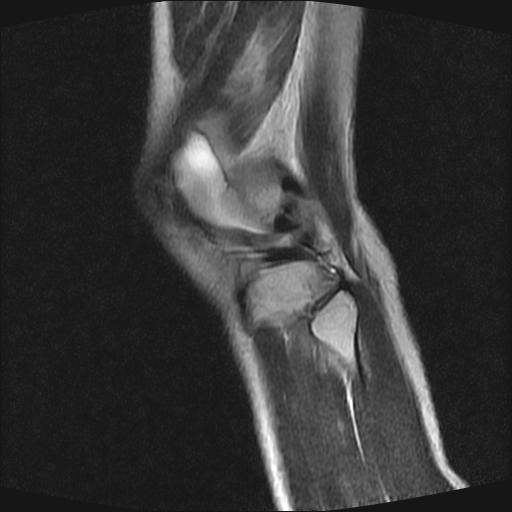

标题: MRI1265:男性40岁,右膝关节 [打印本页]

标题: MRI1265:男性40岁,右膝关节

40岁男性,右膝关节外伤,x光平片示,髁间隆突撕脱骨折。

1、前交叉韧带撕裂;

2、外侧半月板后角撕裂;

3、关节腔积液。

前交叉韧带撕裂,关节腔积液.

半月板1-2级损伤   前交叉韧带撕裂伤   关节腔少量积液  诸骨未见新鲜外伤性改变

髁间隆突撕脱骨折;内侧副韧带损伤。

内侧副韧带撕裂及关节腔积液是肯定的,但是前交叉撕裂确定吗?会不会有容积效应的因素,因为前一张前交叉显示清楚,连续性良好,且较光滑。请问楼主有关节镜支持吗?我们医院也经常有这样的患者,但苦于没有关节镜,而无法对照、证实(除非完全断裂),出现了不同的诊断结果只能毫无意义的争论。

1、前交叉韧、内侧副韧带撕裂;

3、关节腔积液。4、髁间脊撕脱骨折。

除了关节积液外并无韧带撕裂,acl胫侧附着点有2束,正常情况下脂肪信号。此病例应加做压脂像以便观察是否有骨损伤。